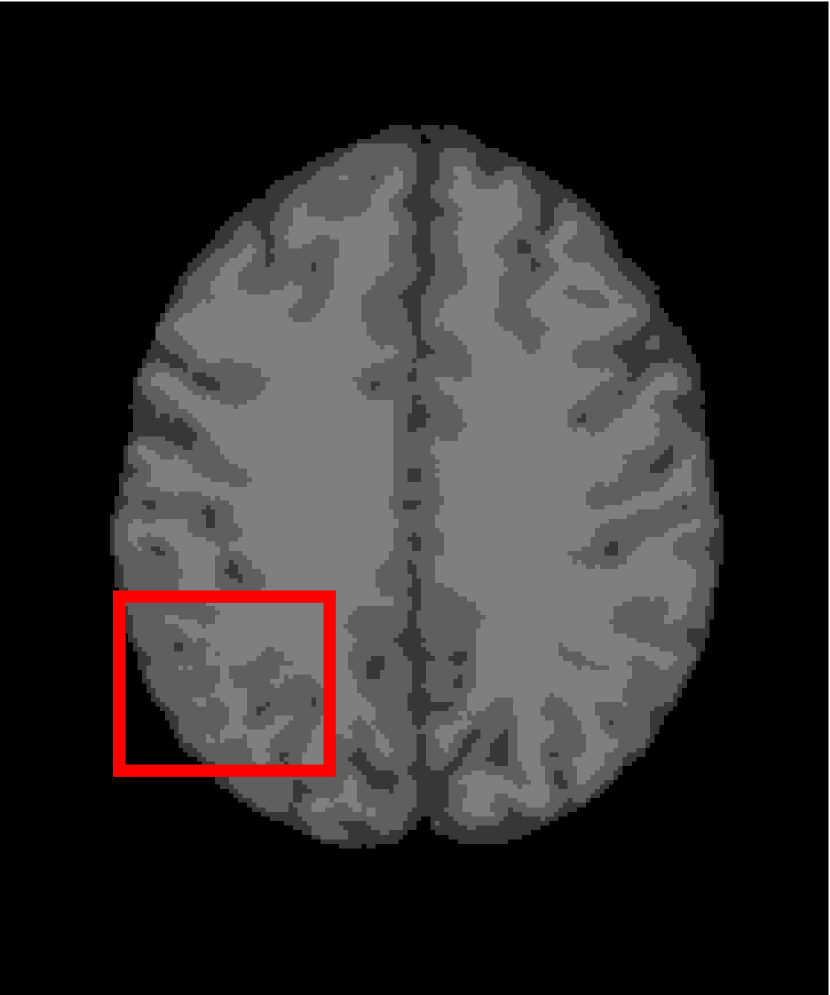

4.4.2 Results on Medical Images

Next, we representatively segment five medical images from BrianWeb. They are represented as five slices in the axial plane with a sequence of 70, 80, 90, 100 and 110, which are generated by T1 modality with slice thickness of 1mm resolution, 9% noise and 20% intensity non-uniformity. Here, we set c=4𝑐4c=4 for all cases. The comparison between WRFCM and its peers are shown in Fig. 9 and Table II. The best values are in bold.

Figure 9: Segmentation results on five medical images. The parameter: ϕ=5.35italic-ϕ5.35\phi=5.35. From top to bottom: noisy images, ground truth, and results of FCM_S1, FCM_S2, FLICM, KWFLICM, FRFCM, WFCM, DSFCM_N, and WRFCM.

By a view of the marked red square in Fig. 9, we find that FCM_S1, FCM_S2, FLICM, KWFLICM and DSFCM_N are vulnerable to noise and intensity non-uniformity. They give rise to the change of topological shapes to some extent. Unlike them, FRFCM and WFCM achieve sufficient noise removal. However, they produce overly smooth contours. Compared with its seven peers, WRFCM can not only suppress noise adequately but also acquire accurate contours. Moreover, it yields the visual result closer to ground truth than its peers. As Table II shows, WRFCM obtains optimal SA, SDS and MCC results for all five medical images. As a conclusion, it outperforms its peers visually and quantitatively.